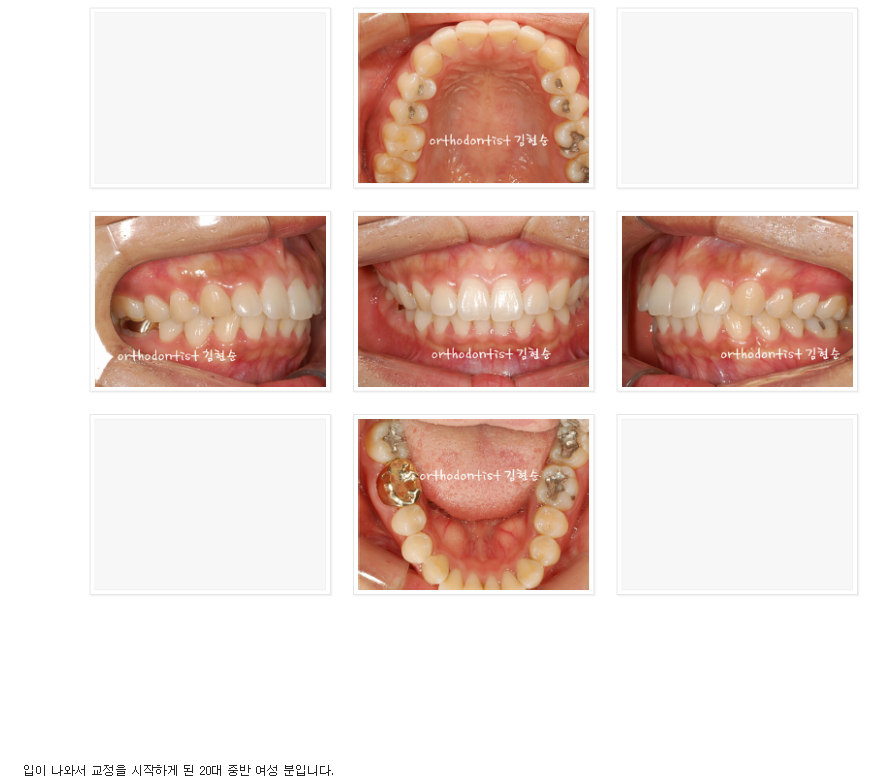

이 분은 앞 얼굴 및 전체적인 인상이 정말 아름다워지셨습니다.

다만 공개된 곳에서 정면 얼굴을 올리시는 것은 결례인 것 같아

차마 올리지 못해 아쉽네요.^^;